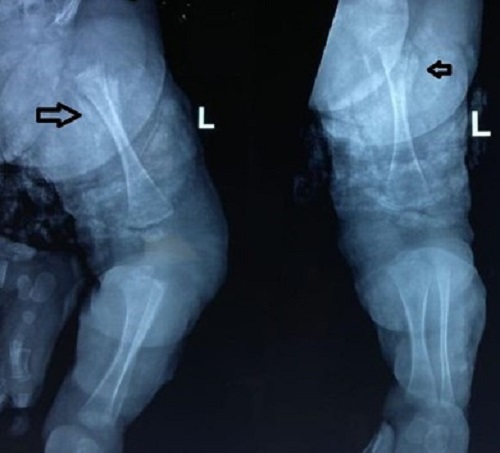

Figure 2

Early X-ray showing normal bone anatomy and soft tissue hypertrophy.

A month-old male baby presented with a complaint of left thigh swelling for 5 days and fever for 2 days. The baby had leukocytosis (TLC = 19200/uL) and a raised CRP (230 mg/L). X-ray Left thigh was within normal limits with only soft tissue changes (Fig. 2). There was a history of a local tap by a local practitioner, which was dry (as per records). Left thigh swelling gradually increased and the baby did not respond to first-line antibiotics for 4 days. Magnetic resonance imaging was planned in view of the suspicion of osteomyelitis and revealed bone marrow edema with osteopenia. There was diffuse edema of left thigh soft tissue with loss of fat planes and thickening suggestive of cellulitis changes. The baby underwent surgical drainage of the pus and received 2 weeks of antibiotics (i.v. and oral) in the postoperative period followed by oral antibiotics for 4 weeks. Pus culture had no growth. Baby is fine at a follow-up period of 2 years.